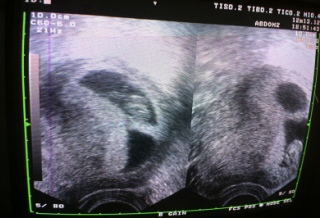

含飴弄「嬰」不是夢 48歲婦博元婦產科試管嬰兒成功鬧雙胞       http://tw.news.yahoo.com/%E5%90%AB%E9%A3%B4%E5%BC%84...

含飴弄「嬰」不是夢 48歲婦博元婦產科試管嬰兒成功鬧雙胞 http://www.flickr.com/photos/41541241@N08/8316666917/in/photostream http://tw.news.yaho...